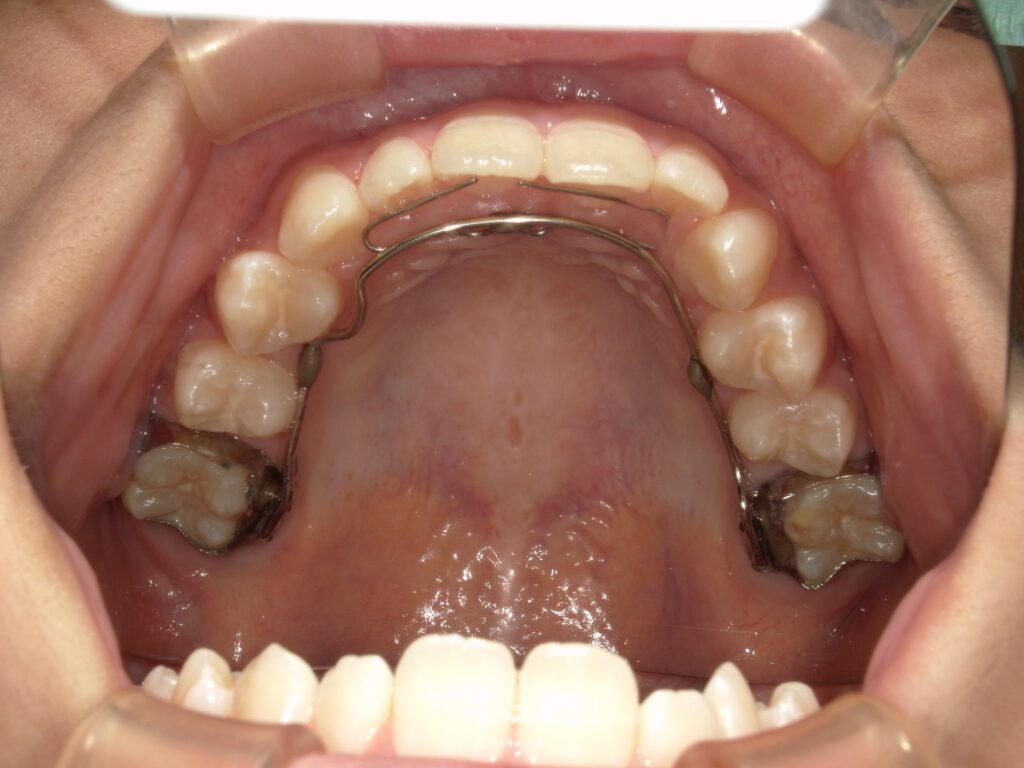

当院では、1期治療の患者様は大抵の方がスペース拡大のため床矯正装置(SPE)を使用しています。十分なスペースを確保できましたら次は固定式装置(LA)に移行し、永久歯に生え変わるまでの間は固定装置を使用していただく流れになっています。

LAでは、裏側のワイヤー部分に細い針金を足すことで、前に押したい歯に力を加えることもできます。

この細い針金を補助弾線といいます。ある程度、前歯や側方歯にがたつきがあったとしても、この補助弾線をつけることで少しはがたつきを改善することができます。